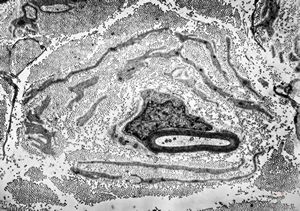

![F,23y. | n.suralis - hypertrophic demyelinating neuropathy [onion bulb] F,23y. | n.suralis - hypertrophic demyelinating neuropathy [onion bulb]](../img/OGDEM/015 Soft tissues/0077.jpg)

F,23y. | n.suralis - hypertrophic demyelinating neuropathy [onion bulb]